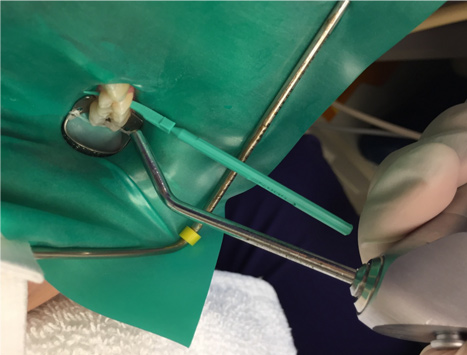

3. Place a rubber dam. Local anesthetic is not necessary, but topical anesthetic may be helpful for patients who find the clamp to be uncomfortable.

4. Remove the separator. If needed to accommodate the applicator, utilize one of the wedges provided in the proximal resin infiltration kit to create more space between the teeth (Figure 4).

5. Insert applicator with resin infiltration material with green side and perforations facing the surface to be treated (Figure 5).